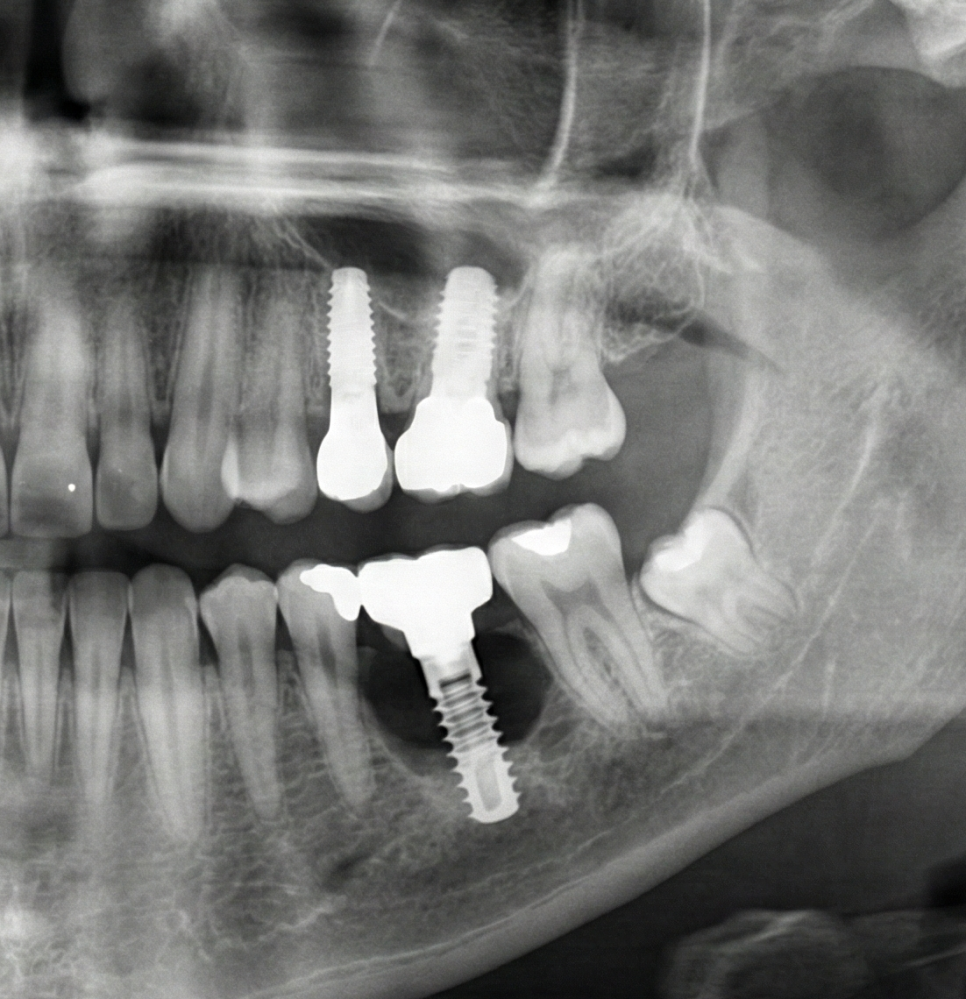

기능 회복을 위한 첫 단추: 뼈이식

뼈가 녹아버린 상태에서는 임플란트를 심고 싶어도

나무를 심을 흙이 부족한 것과 같은 상황이 됩니다.

이때 필요한 것이 바로 '골이식(뼈이식)'입니다.

부족한 부분에 이식재를 채워 넣어

인공치아가 단단히 고정될 수 있는

환경을 만드는 것이죠.

임플란트 식립과 골유착의 과정

기반이 준비되었다면

이제 본격적으로 임플란트를 식립하게 됩니다.

단순히 심는 것으로 끝나는 것이 아니라,

식립된 임플란트와 환자 본인의 뼈가

단단하게 붙는 '골유착' 기간이 필요하죠.

이 기간은 환자분의

골질이나 건강 상태에 따라

수개월 정도 소요될 수 있으며,

이 시기를 얼마나 안정적으로 보내느냐가

전체 치료의 성패를 좌우하기도 합니다.

이 과정에서 발생할 수 있는 불편을 줄이고

성공률을 높이기 위해 디지털 장비를 활용해

식립 위치를 결정합니다.